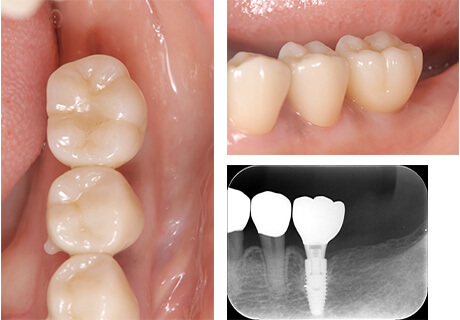

技工士が歯の色に合わせて一つ一つ丁寧にセラミックインレーを製作します。

セラミックインレーの装着時には写真のようにラバーダムというゴムのシートを使うことにより接着力が増します。

接着力が増すと虫歯の再発率を減らすことにつながります。

治療のリスク

虫歯の範囲が大きいとクラウンによる治療の適応になります。

治療回数

2回